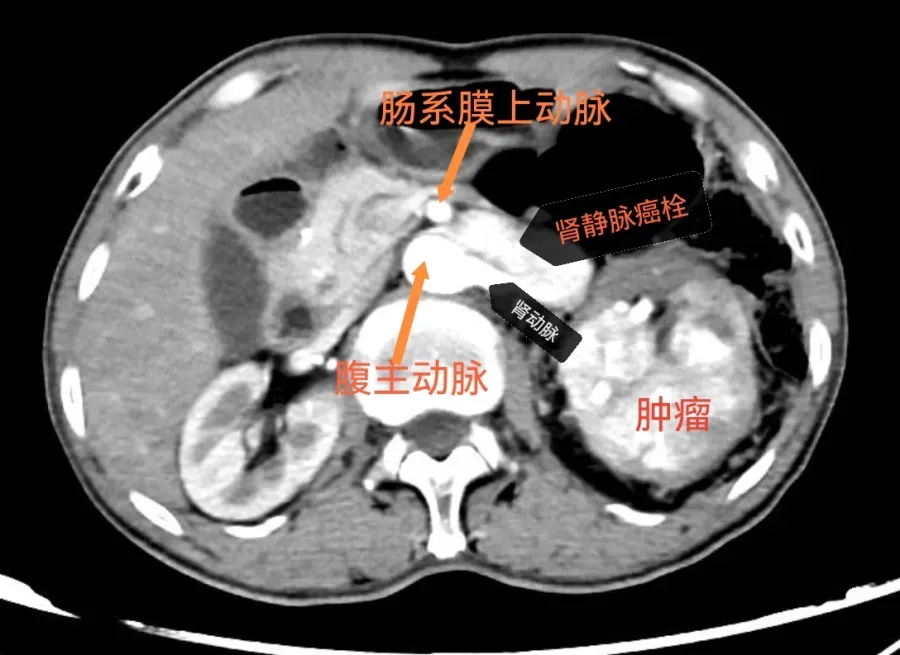

患者是一位65岁老年男性,除一次轻微尿血外,无其他阳性症状体征。泌尿外科副主任医师索杰却敏锐捕捉到这一信息,直接收住入院详细检查,很快B超发现了异常,约10cm的肿瘤占据大半个肾脏,而且瘤栓已经长入左肾静脉,近端达腹主动脉和肠系膜上动脉夹角处,瘤体和腰大肌界限不清。

针对这个患者的病情,宝鸡市中心医院姜谭院区泌尿外科主任刘建舟指导团队充分利用姜谭院区达芬奇机器人的精细操作优势,放大视野、轻柔游离,将隐藏在宽大肾静脉下方的肾动脉牵出来、钳夹阻断,再将肾静脉游离至癌栓近端,双重阻断,此处已接近腹主动脉、肠系膜上动脉、胰尾等重要器官,一旦损伤后果严重,但刘主任高超的技艺最终令患者化险为夷,术后恢复良好,拟近期出院。